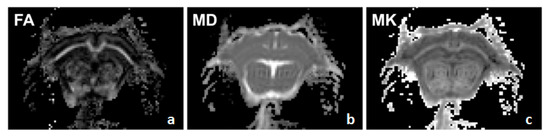

2.3. Data Processing

3.2. Age Dependency of Whole Brain T2, FA, Diffusivity, and Kurtosis Measures